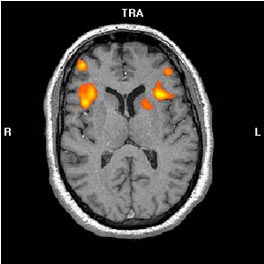

En nuestra experiencia clínica con pacientes con ELT izquierda encontramos resultados que concuerdan con la literatura previa, ya que existe una organización atípica del lenguaje en este tipo de pacientes donde se obtienen activaciones de menor dominancia izquierda (ver Figuras 1A Y 1B).

Activación cerebral bilateral durante la tarea de fluidez fonética (1A) y generación verbal (1B) en un paciente con ELT izquierda con una dominancia manual preferentemente diestra evaluada mediante el Edinburgh Handedness Inventory

| 1A.- Fluidez fonética |

1B.- Generación verbal |